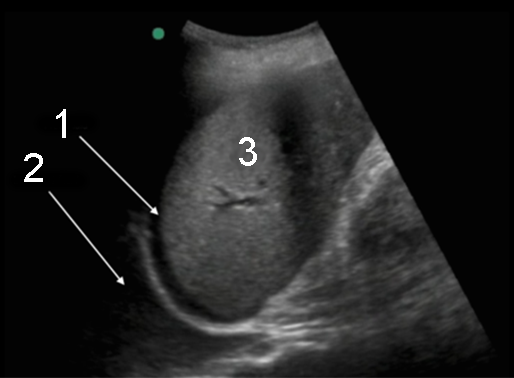

游离液体

左胸腔积液

脾脏